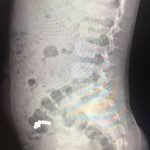

Нещодавно у місцеве хірургічне відділення поступив п’ятирічний хлопчик – за 17 днів до цього він проковтнув сім дрібних магнітних кульок з іграшки. І хоч скарги на самопочуття у дитини були відсутні, під час рентгенологічного дослідження діагностували наявність магнітів в кишечнику, які не просуваються протягом 10 днів. Це стало показанням до оперативного втручання, пише “Галка”.

Вже під час операції медики виявили зрощення стінки тонкої кишки, де розташовані 4 магніти, із стінкою сліпої кишки, де виявлено 3 магніти. Фахівці видалили зайві предмети та провели необхідні лікувальні маніпуляції з кишками. В підсумку обійшлося без небезпечних ускладнень.